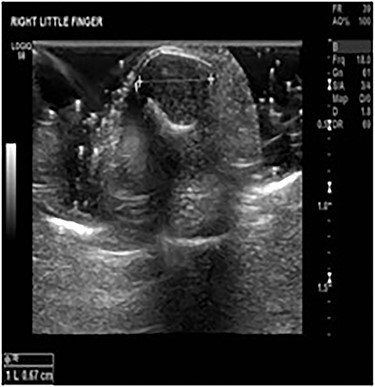

At the clinic, the patient was examined thoroughly. He was suffering from a constant deep throbbing pain (9/10 numeric pain scale) throughout the day and night. He required non-steroidal anti inflammatory drugs (NSAIDs) and opiates regularly to alleviate the pain. Yet, the itching of the ulnar aspect of the hand and little finger was not relieved with medication. The patient described paroxysmal pain on dishwashing, especially with cold water. Clinical examination showed exquisite pressure tenderness over the tip of the right little finger with positive Love’s pin test and Hildreth’s test. The signs, symptoms and clinical tests supposed the condition to be a GT. X-rays, ultrasound scan and contrast-enhanced MRI confirmed the lesion of 16 × 8 × 7mm to be a GT (Figs 1 and 2).

Little finger MSK ultrasound—19 July 2018 ‘16 × 8 × 7 mm’ soft tissue lesion involving the nail bed and wrapping around the terminal phalanx of the right little finger suspicious for a GT.